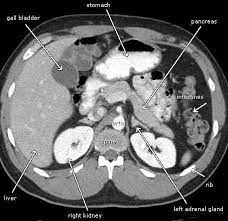

Abdominal pain can stem from a variety of issues, ranging from minor digestive troubles to serious conditions like tumors or internal bleeding. Without proper diagnosis, the anxiety surrounding these symptoms can be overwhelming. For Meena, the fear of the unknown was paralyzing. Her family doctor recommended an abdominal CT scan, a sophisticated imaging technique that provides detailed cross-sectional images of the abdomen, enabling doctors to accurately diagnose internal issues.